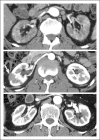

Recent findings: A wide range of renal manifestations of IgG4-RD, that is TIN, membranous glomerulonephritis (MGN) and other glomerular lesions, and pyelitis, are collectively referred to as IgG4-RKD. Clinically, decreased renal function, or characteristic imaging findings such as multiple low-density lesions on contrast-enhanced computed tomography or diffuse thickening of the renal pelvic wall, are typical presenting features. Although a rapid response to corticosteroid therapy is a very important feature of IgG4-TIN, in cases in which renal function is moderately to severely decreased before therapy, only partial recovery of renal function is obtained.